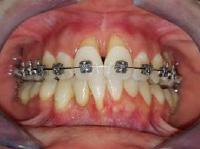

Lâexamen exobuccal Ă©tait sans particularitĂ©s. Lâexamen endobuccal a objectivĂ© une inflammation marginale modĂ©rĂ©e Ă sĂ©vĂšre gĂ©nĂ©ralisĂ©e avec un indice dâOleary Ă 68%, un indice gingival (BoP = Bleeding on Probing) Ă 76%, et un trama occlusal sur 42 (Figure 1). Le bilan parodontal montre des sites avec une profondeur de sondage (PS) de 12mm, et plus de 50% des dents prĂ©sentant une perte dâattache â„ 5mm. Le bilan radiographique a montrĂ© des pertes osseuses terminales, avec un rapport perte osseuse/Ăąge Ă 4,5 (Figure 1)

Le diagnostic de parodontite stade IV grade C généralisé a été proposé (1), avec un pronostic irrationnel au traitement pour les dents 25, 36, 42 et défavorable pour 11, 21, 35, 46 (2).

La thĂ©rapeutique Ă©tiologique a consistĂ© en une Ă©ducation Ă lâhygiĂšne bucco-dentaire, une Ă©limination des facteurs de rĂ©tention de plaque, lâextraction 42+rĂ©section radiculaire et rĂ©alisation dâune contention en fibre de verre avec la couronne ; dâune instrumentation non chirurgicale supra et sous gingivale

par quadrant (3) combinĂ©e Ă une antibiothĂ©rapie (3,4). Une chirurgie avec lambeau dâaccĂšs selon la technique du lambeau avec incision intrasulculaire (open flap) a Ă©tĂ© rĂ©alisĂ©e sur la 46. Une thĂ©rapie parodontale de soutien associĂ©e Ă une phase correctrice a Ă©tĂ© mise en place aprĂšs la thĂ©rapie parodontale active (5). La rĂ©habilitation orale a consistĂ© dans un premier temps Ă rĂ©aliser une correction orthodontique (Figure 2) ; et dans un second temps la conception dâune Ă©pithĂšse gingivale (Figure 3)

AprĂšs 6 mois, pas de profondeurs de poches â„ 6mm, avec un indice de plaque Ă 9% et un indice gingival < 10%. La thĂ©rapeutique non chirurgicale a permis un gain dâattache

stable qui sâest traduit par une diminution des profondeurs de sondage en regard de la 11, 21, et 36 dont le pronostic Ă©tait dĂ©favorable, mais aussi lâapparition dâimportantes rĂ©cessions postthĂ©rapeutique (Figure 4). La chirurgie avec lambeau dâaccĂšs a permis Ă©galement dâamĂ©liorer le niveau osseux de la 46. Le pronostic gĂ©nĂ©ral Ă long terme de la patiente a Ă©tĂ© amĂ©liorĂ©.

La réévaluation Ă 3 mois a montrĂ© une amĂ©lioration de lâĂ©tat parodontal avec plus de 90% de sites prĂ©sentant des PS †4mm (3). LâefficacitĂ© du dĂ©bridement mĂ©canique non chirurgical associĂ© Ă un bon contrĂŽle de plaque individuel dans le traitement des parodontites sĂ©vĂšres a Ă©tĂ© largement documentĂ©e dans plusieurs revues systĂ©matiques (6). Toutefois, la prĂ©sence dâune poche rĂ©siduelle de 6mm avec saignement au sondage sur la 46 reprĂ©sentait un rĂ©sultat incomplet et a nĂ©cessitĂ© dans notre cas un traitement chirurgical par lambeau dâaccĂšs afin dâĂ©viter la progression de la maladie (7).

La rĂ©cession post-thĂ©rapeutique est une observation commune aprĂšs une instrumentation non chirurgicale, particuliĂšrement au niveau des poches profondes et/ou dâun phĂ©notype gingival fin. Notre patiente prĂ©sentait une RT3 sur les incisives centrales rendant son sourire inesthĂ©tique (trou noir). Les restaurations dentaires directes et indirectes et/ou Ă©pithĂšses pouvant ĂȘtre envisagĂ©es (5) ; nous avons optĂ© pour une solution moins invasive en rĂ©alisant une Ă©pithĂšse gingivale. Peu coĂ»teuse et pratique, elle a permis dâoptimiser le rĂ©sultat esthĂ©tique et fonctionnel dans un contexte socio-Ă©conomique limitĂ©.

Figure 4 : (a) Vue clinique Ă 6 mois ; (b) bilan radiographique Ă 3mois (b) ; (c) Retro alvĂ©olaire sur la 46 avant et aprĂšs lambeau dâassainissement